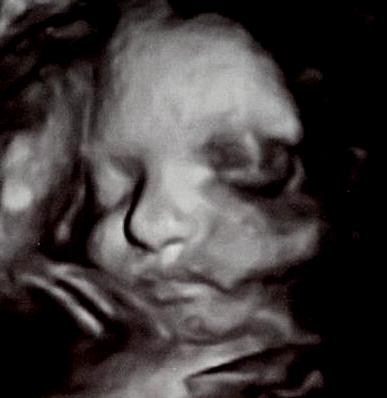

Så har vi for anden gang været til 3D scanning - en gratis én af slagsen fordi første forsøg mislykkedes totalt. Vores 'Mini' gemte sig fuldstændig væk, lagde sig med hænderne op foran ansigtet og videre lå navlesnoren ind foran ansigtet og lavede nogle grimme skygger på billderne, så det ser ud som om lillefis har et blåt øje

Vi havde egentligt besluttet ikke at få lavet en 3D scanning (da jeg synes det er lidt for dyrt og poppet), men min kæreste havde alligevel bestilt tid som en overraskelse til mig, hvilket jeg naturligvis blev super glad for. Nu føles det bare en lille smule tamt, da vi på de to forsøg stadig ikke har fået de billeder, som vi gerne ville have haft, MEN uanset var det dejligt at se den lille pige igen, se hende smile, spytte vand, række tunge og bevæge sig vildt og voldsomt rundt

Selvom billederne er ret dårlige er der flere af vores venner + familie, der har kommenteret, at de tydeligt kan se nogle af mine ansigtstræk hos hende, det går lige i

på mig.